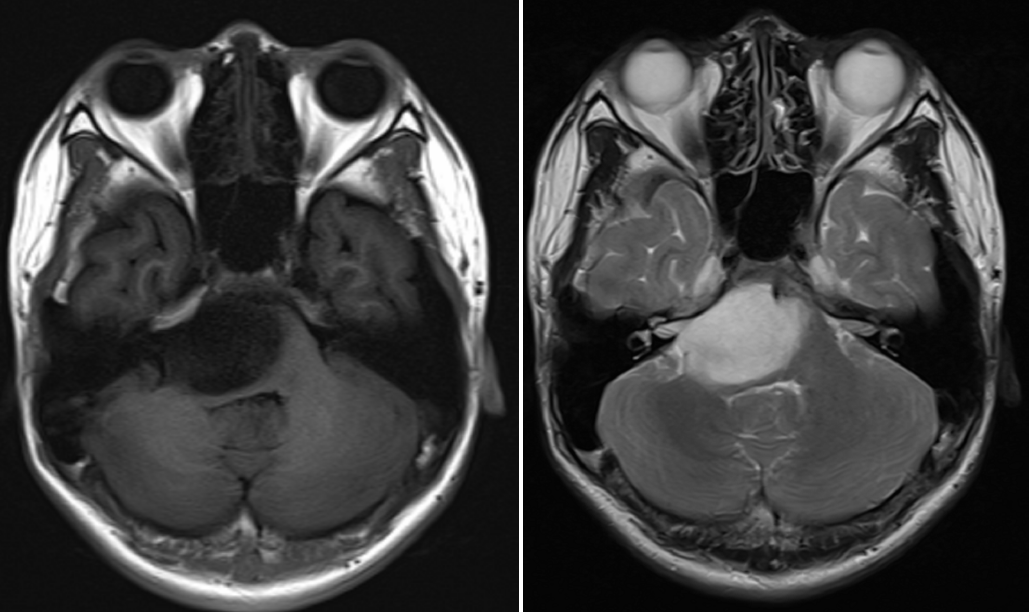

入院后进一步增强MRI检查,诊断脑干胶质瘤可能性大,右侧桥脑为主,考虑弥漫性内生性型脑桥胶质瘤可能性大。同时加做灌注成像,了解肿瘤灌注情况(图1)。考虑肿瘤偏侧生长,家属手术意愿强烈,科室讨论可以考虑手术治疗。手术目的:明确病理,并给予肿瘤减容,减缓肿瘤生长速度,提高后续综合治疗效果。

图1.头颅平扫+增强+灌注MR示:脑干见约32*36*34mm大小类圆形长T1长T2异常信号,右侧桥脑为主,边缘尚清,增强后未见明显强化,四脑室稍受压;余脑实质未见明显异常信号;中线结构居中。灌注成像未见灌注增高。